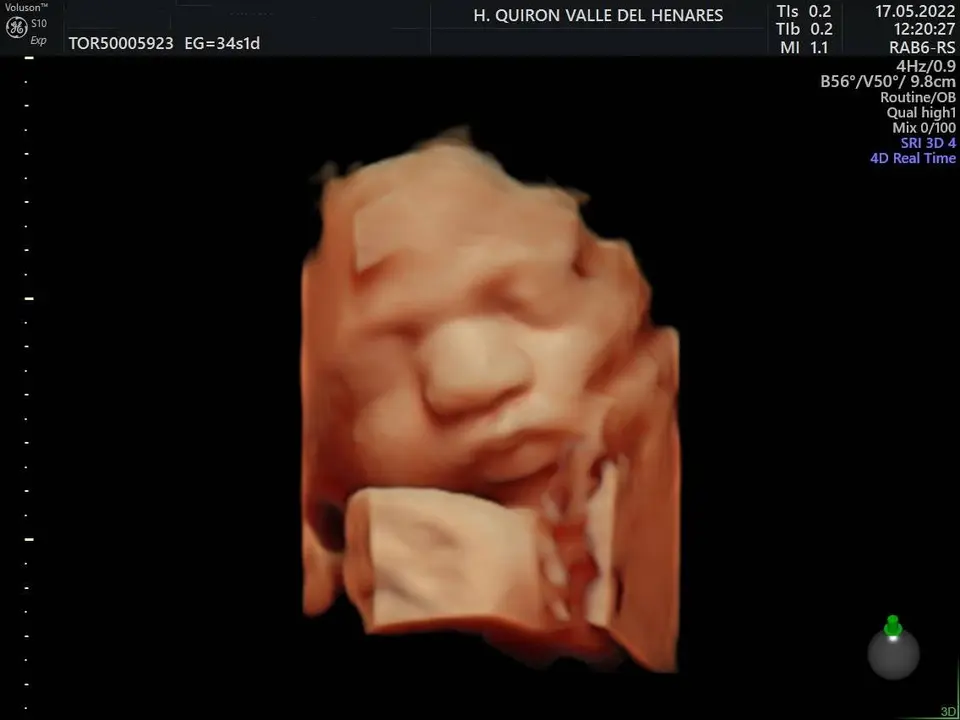

El Hospital Quirónsalud Valle del Henares, en Torrejón de Ardoz, ofrece la posibilidad de realizar ecografías gestacionales 5D. Este tipo de exploración permite obtener una imagen muy realista del bebé y se puede realizar en cualquier etapa de la gestación -aunque lo recomendado es realizarla entre las semanas 28 y 32 de gestación, ya que técnicamente es el mejor momento y es mucho más probable obtener imágenes de buena calidad-.

La exploración tiene una duración aproximada de 30 minutos en los que los padres y los familiares que ellos decidan (se permite el paso de hasta 3 acompañantes, dada la situación epidemiológica actual) pueden disfrutar de ver a su bebé en una pantalla de gran formato.

Al final de la prueba, se entrega a la familia un informe de la ecografía y un soporte digital que contiene las imágenes y los vídeos realizados. Las ecografías 4D y 5D son también llamadas emocionales por la explosión de sensaciones que genera cuando la madre ve por primera vez la imagen del bebé que espera.

«Realizar esta ecografía con nuestro equipo de diagnóstico prenatal tiene un valor añadido», señala la Dra. Rocío Vellido Cotelo, Jefa Asociada de Ginecología y Obstetricia del Hospital Quirónsalud Valle del Henares, «dado que quien realiza la prueba es un especialista en la materia, siempre se completa la exploración con un examen morfológico y de perfil biofísico fetal, que permita valorar el estado de bienestar del bebé más allá de la captura de vídeos y fotografías».